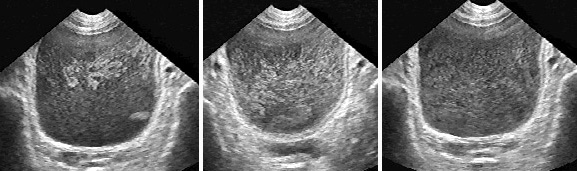

Установить положение точечных устий помогают выбросы из мочеточников (рис. 3). Это явление можно наблюдать в 30−40% исследований мочевого пузыря. при форсировании мочевыделения диуретиками выявляемость эффекта достигает 70−80% [4,17]. В цветном допплеровском режиме выбросы можно обнаружить практически во всех случаях. Визуализация этого сонографического феномена связана с эффектом псевдоконтрастирования турбулентной струи мочи, выбрасываемой в мочевой пузырь при сокращении нижнего цистоида мочеточника. На контрастность визуализации выбросов влияет также разность плотностей пузырной и мочеточниковой мочи [3,10].

Рис. 3. Сонограммы мочевого пузыря в норме и при аномалиях развития почек и мочеточников. Выбросы из мочеточников помогают установить положение и число устий, подтвердить тем самым наличие одной, двух или трех функционирующих почек (Поперечное сканирование, секторный датчик 5 МГц, “Siemens SL-1”).